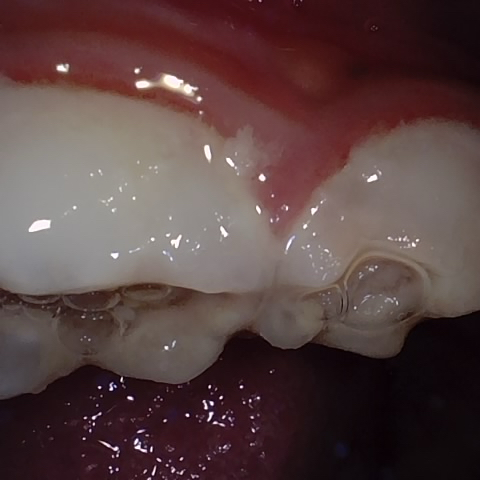

Image 302 / 400

NHD25463

Annotated as "Good"

Original Image Rendering Image